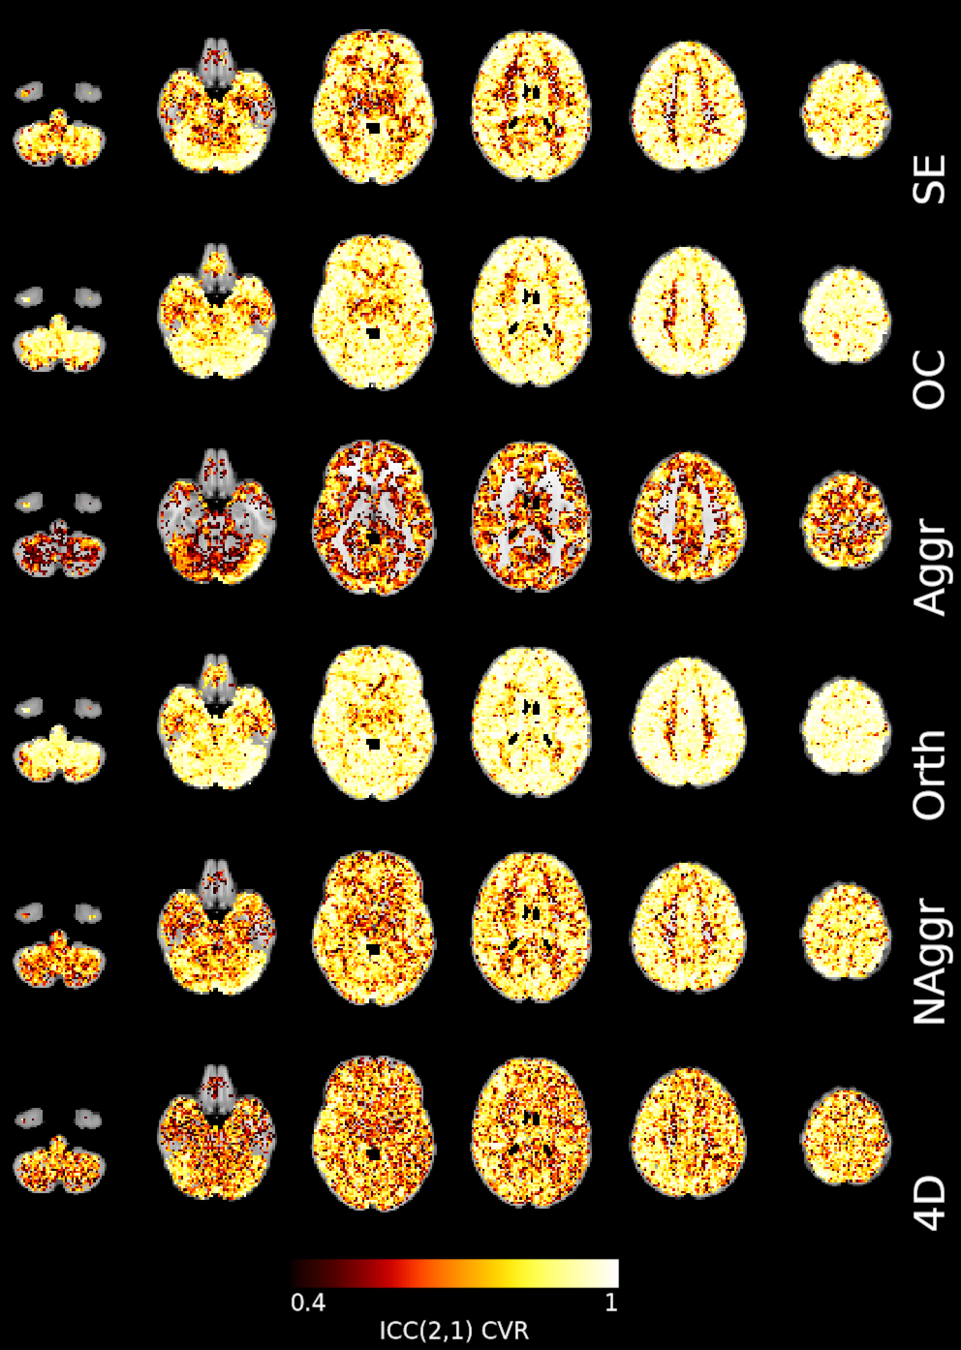

Results: CVR amplitude maps

Moia et al. 2021 (NeuroImage)

Reliability [ICC (2,1)]

Moia et al. 2021 (NeuroImage)

OC-MPR vs ME-CON

ME-CON should be better than OC-MPR in temporal-dependent application